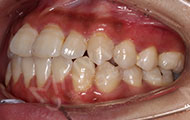

回老地方坐坐,找老朋友聚聚。矫正快一年了,牙齿渐渐开始整齐了,矫正效果不错哦~